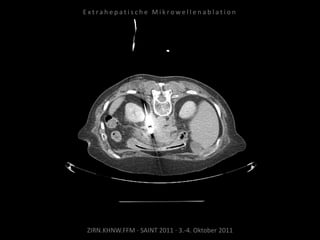

Erneute Ablation von 2 peritonealen

Metastasen am 09.09.2010.

Metastase kaudal der linken Niere:

Apikal 2 Nadelpositionen.

Kaudal 1 Nadelposition.